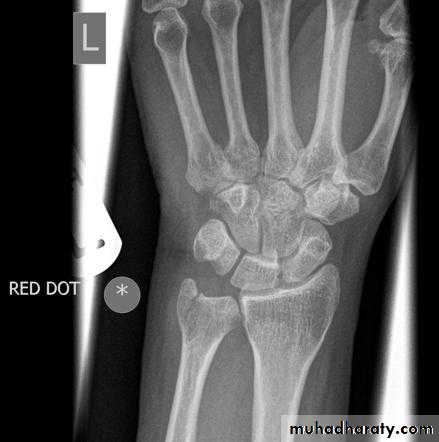

• عمليا يتم تصوير الرسغ والمرفق والكتف لمن يبدوا ظاهرا دون سن العشرين عاما من العمر. ويصور الحرقف لمن بدا في اواسط العقد الثالث من العمر او اقل, والنهاية الانسية للترقوة والتحام القص بالرهابة لمن تجاوز ذلك.

55• معدل ظهور والتحام المراكز التعظمية تبعا للعمر:

• 1) عند الولادة يظهر المركز التعظمي للنهاية السفلى للفخذ والمركز التعظمي لرأس عظم العضد.

• 2) في السنة الاولى( نهاية الشهر الثالث) يظهر (متع) للعظم الرؤيسي والشصي

• وفي الشهر السابع يظهر متع للنهاية السفلى للكعبرة, وفي الشهر العاشر يظهر

• متع للعظم المثلث من عظام الرسغ.

• 2) السنة الثانية يظهر المركز التعظمي للعظم الهلالي الرسغي.

• 3) في نهاية السنة الرابعة يظهر متع لرأس الكعبرة.

• 4) وفي بداية السنة الخامسة يظهر متع للعظم المربع المنحرف وفي نهاية السنة االخامسة يظهر المركز التعظمي لعظمي شبه المنحرف والزورقي الرسغيين.

• 5) في سن السادسة يظهر متع للقمة الانسية لعظم العضد والنهاية السفلية لعظم الزند.

6) في السنة الثامنة ونصف يظهر متع لبكرة العضد.

7) في نهاية السنة التاسعة يظهر متع للنتوء المرفقي لعظم الزند والعظم الحمصي.

8) في نهاية السنة العاشرة يظهر متع اللقمة الوحشية للعضد.

معدل التحام مراكز التعظم:

1) في سن 13-14 سنة تلتحم البكرة بعمد العضد.

2) في سن 14-15 يلتحم راس الكعبرة بالعمد والنتوء المرفقي بالزند.

3) في سن 16-17 سنة تلتحم اللقمة الانسية بعمد العضد.

574) في سن 17-18 تلتحم النهايتان السفليتان للكعبر والزند كل مع عمده.

5) في سن 18-19 يلتحم راس العضد بعمده.

6) وفي سن 25 سنة يلتحم عرف الحرقف بالحرقف والنهاية الانسية للترقوة بالترقوة.